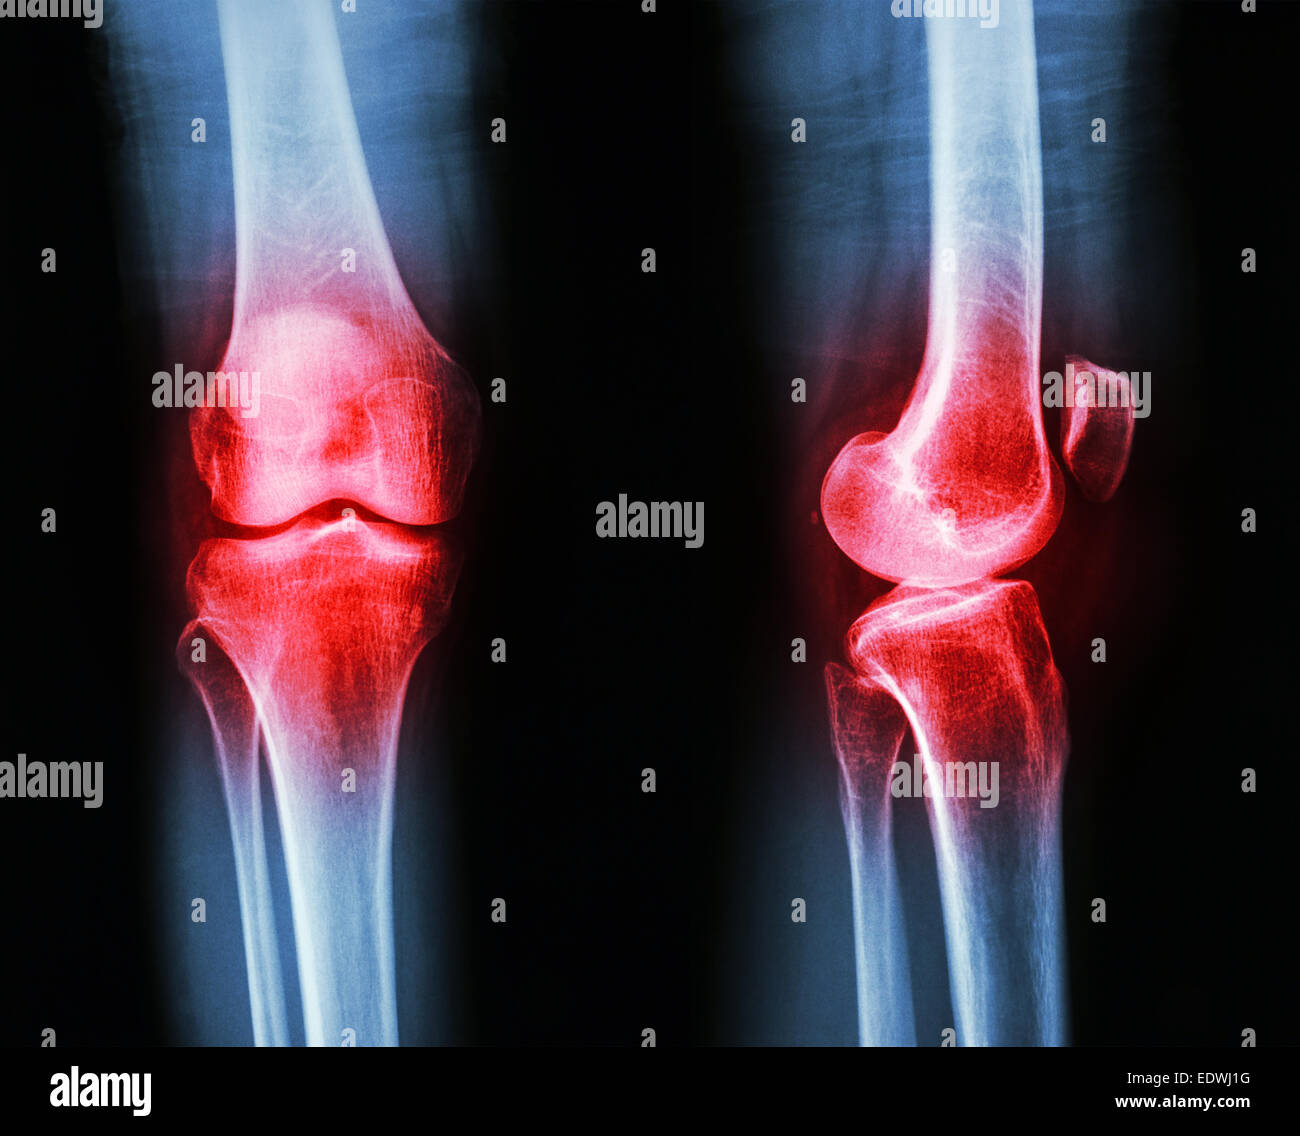

Film x-ray AP/GENOU Arthrose : latéral (Inflammation au genou) Banque D'Imageshttps://www.alamyimages.fr/image-license-details/?v=1https://www.alamyimages.fr/photo-image-film-x-ray-ap-genou-arthrose-lateral-inflammation-au-genou-77394958.html

Film x-ray AP/GENOU Arthrose : latéral (Inflammation au genou) Banque D'Imageshttps://www.alamyimages.fr/image-license-details/?v=1https://www.alamyimages.fr/photo-image-film-x-ray-ap-genou-arthrose-lateral-inflammation-au-genou-77394958.htmlRFEDWJ1J–Film x-ray AP/GENOU Arthrose : latéral (Inflammation au genou)

Film x-ray AP/GENOU Arthrose : latéral (Inflammation au genou) Banque D'Imageshttps://www.alamyimages.fr/image-license-details/?v=1https://www.alamyimages.fr/photo-image-film-x-ray-ap-genou-arthrose-lateral-inflammation-au-genou-77394956.html

Film x-ray AP/GENOU Arthrose : latéral (Inflammation au genou) Banque D'Imageshttps://www.alamyimages.fr/image-license-details/?v=1https://www.alamyimages.fr/photo-image-film-x-ray-ap-genou-arthrose-lateral-inflammation-au-genou-77394956.htmlRFEDWJ1G–Film x-ray AP/GENOU Arthrose : latéral (Inflammation au genou)